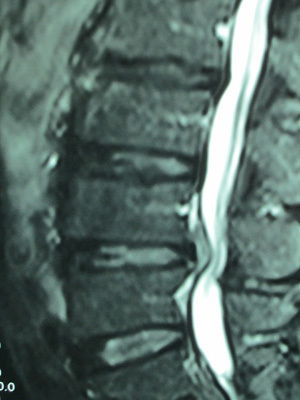

病院で検査してもらったところ「L4とL5椎間板髄核は脱出がみられ、脊柱管狭窄を呈しています」とのこと。

病院でMRIを撮ってもらったところ「椎間板ヘルニアによる坐骨神経痛」と診断された。